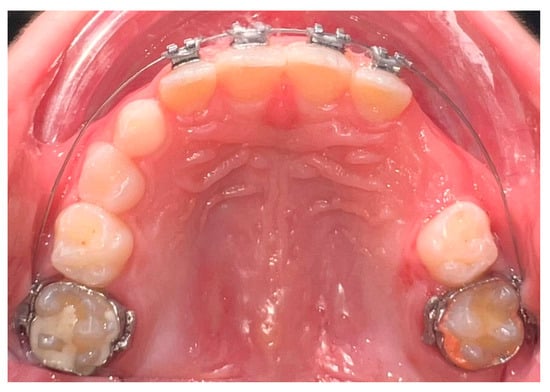

| Da Silva, V. et al., 2023 [86] | Randomized clinical trial | 32 children (7–11 years old) | Compare efficacy and efficiency of clear aligners vs. 2 × 4 appliances in regard to mixed dentition | Digital dental models and 3D software were used. Patients were randomized into clear aligner or 2 × 4 fixed-appliance groups and treated for ~8 months. | Both methods showed similar efficacy; appliance choice can be based on clinician and family preference. |

| Cruz, J. et al., 2023 [87] | Prospective non-randomized clinical study | 48 children (24 treated, 24 controls) | Evaluate upper-arch dimensional changes using 2 × 4 appliance with NiTi spring in MD phase. | Lateral radiographs, cast models, CuNiTi wires, and NiTi open springs were used. Treated patients were compared to growth-only controls. | 2 × 4 appliance effectively increased arch perimeter and depth and maintained incisor position. |